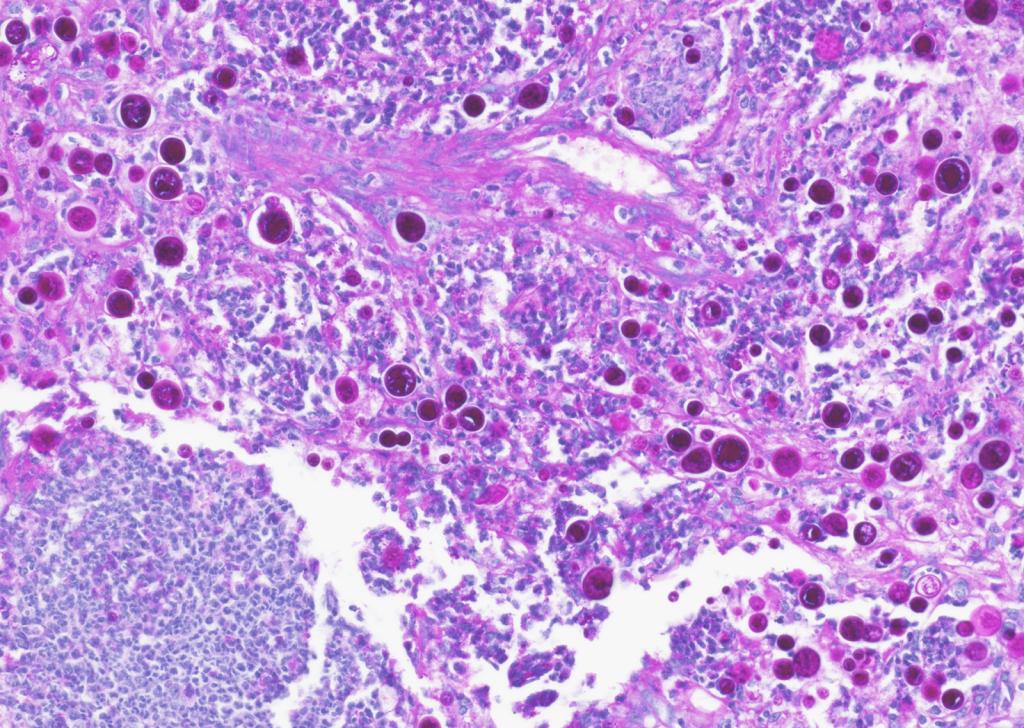

Most people who breathe in cocci spores — about six in 10 — won’t develop symptoms. But the 40% of exposed people whose immune systems can’t or won’t fight off the fungus develop symptoms such as fatigue, muscle aches, coughing, and rash that can last weeks or months. In the 5 -10% of symptomatic cases where the fungus invades the vital organs, the death rate is as high as 25%. The pathogen is so powerful that the U.S. army weighed whether to develop it into a bioterrorism weapon in the 1960s. (A histological slide of valley fever spores in the lung tissue of a dog is shown below.)

A histological slide of valley fever spores in the lung tissue of a dog.

Lisa Shubitz // Valley Fever Center for Excellence